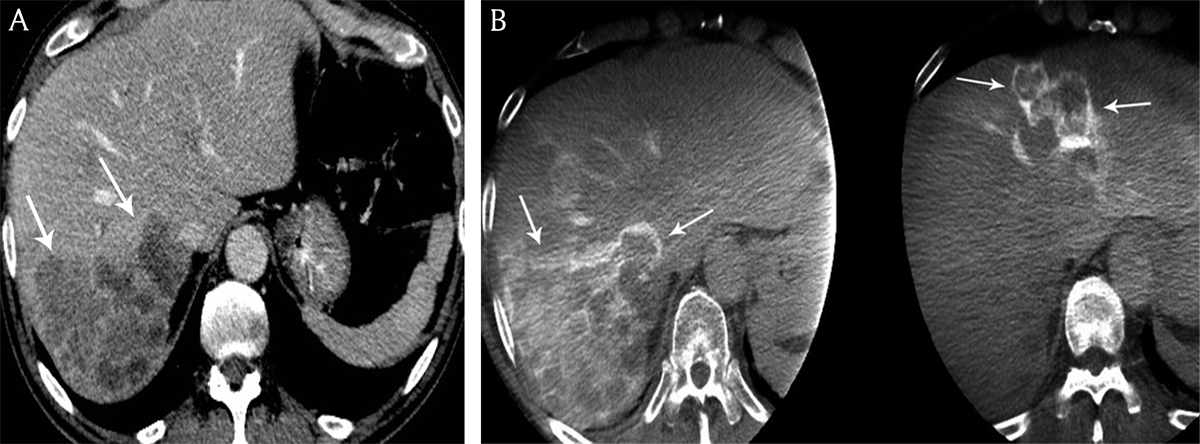

Tumor contrast enhancement

The density and the rim enhancement of the liver metastases on both CE-CT and DP-CBCT images are summarized in Table 3 (Figure 5).

Figure 5

A) Contrast-enhanced computed tomography and B) cone beam computed tomography in a 68-year-old man presenting with bilobar colon cancer liver metastases. Contrast-enhancement of the peripheral tumoral rim is hyperdense to the residual liver parenchyma on cone beam computed tomography versus contrast-enhanced computed tomography.